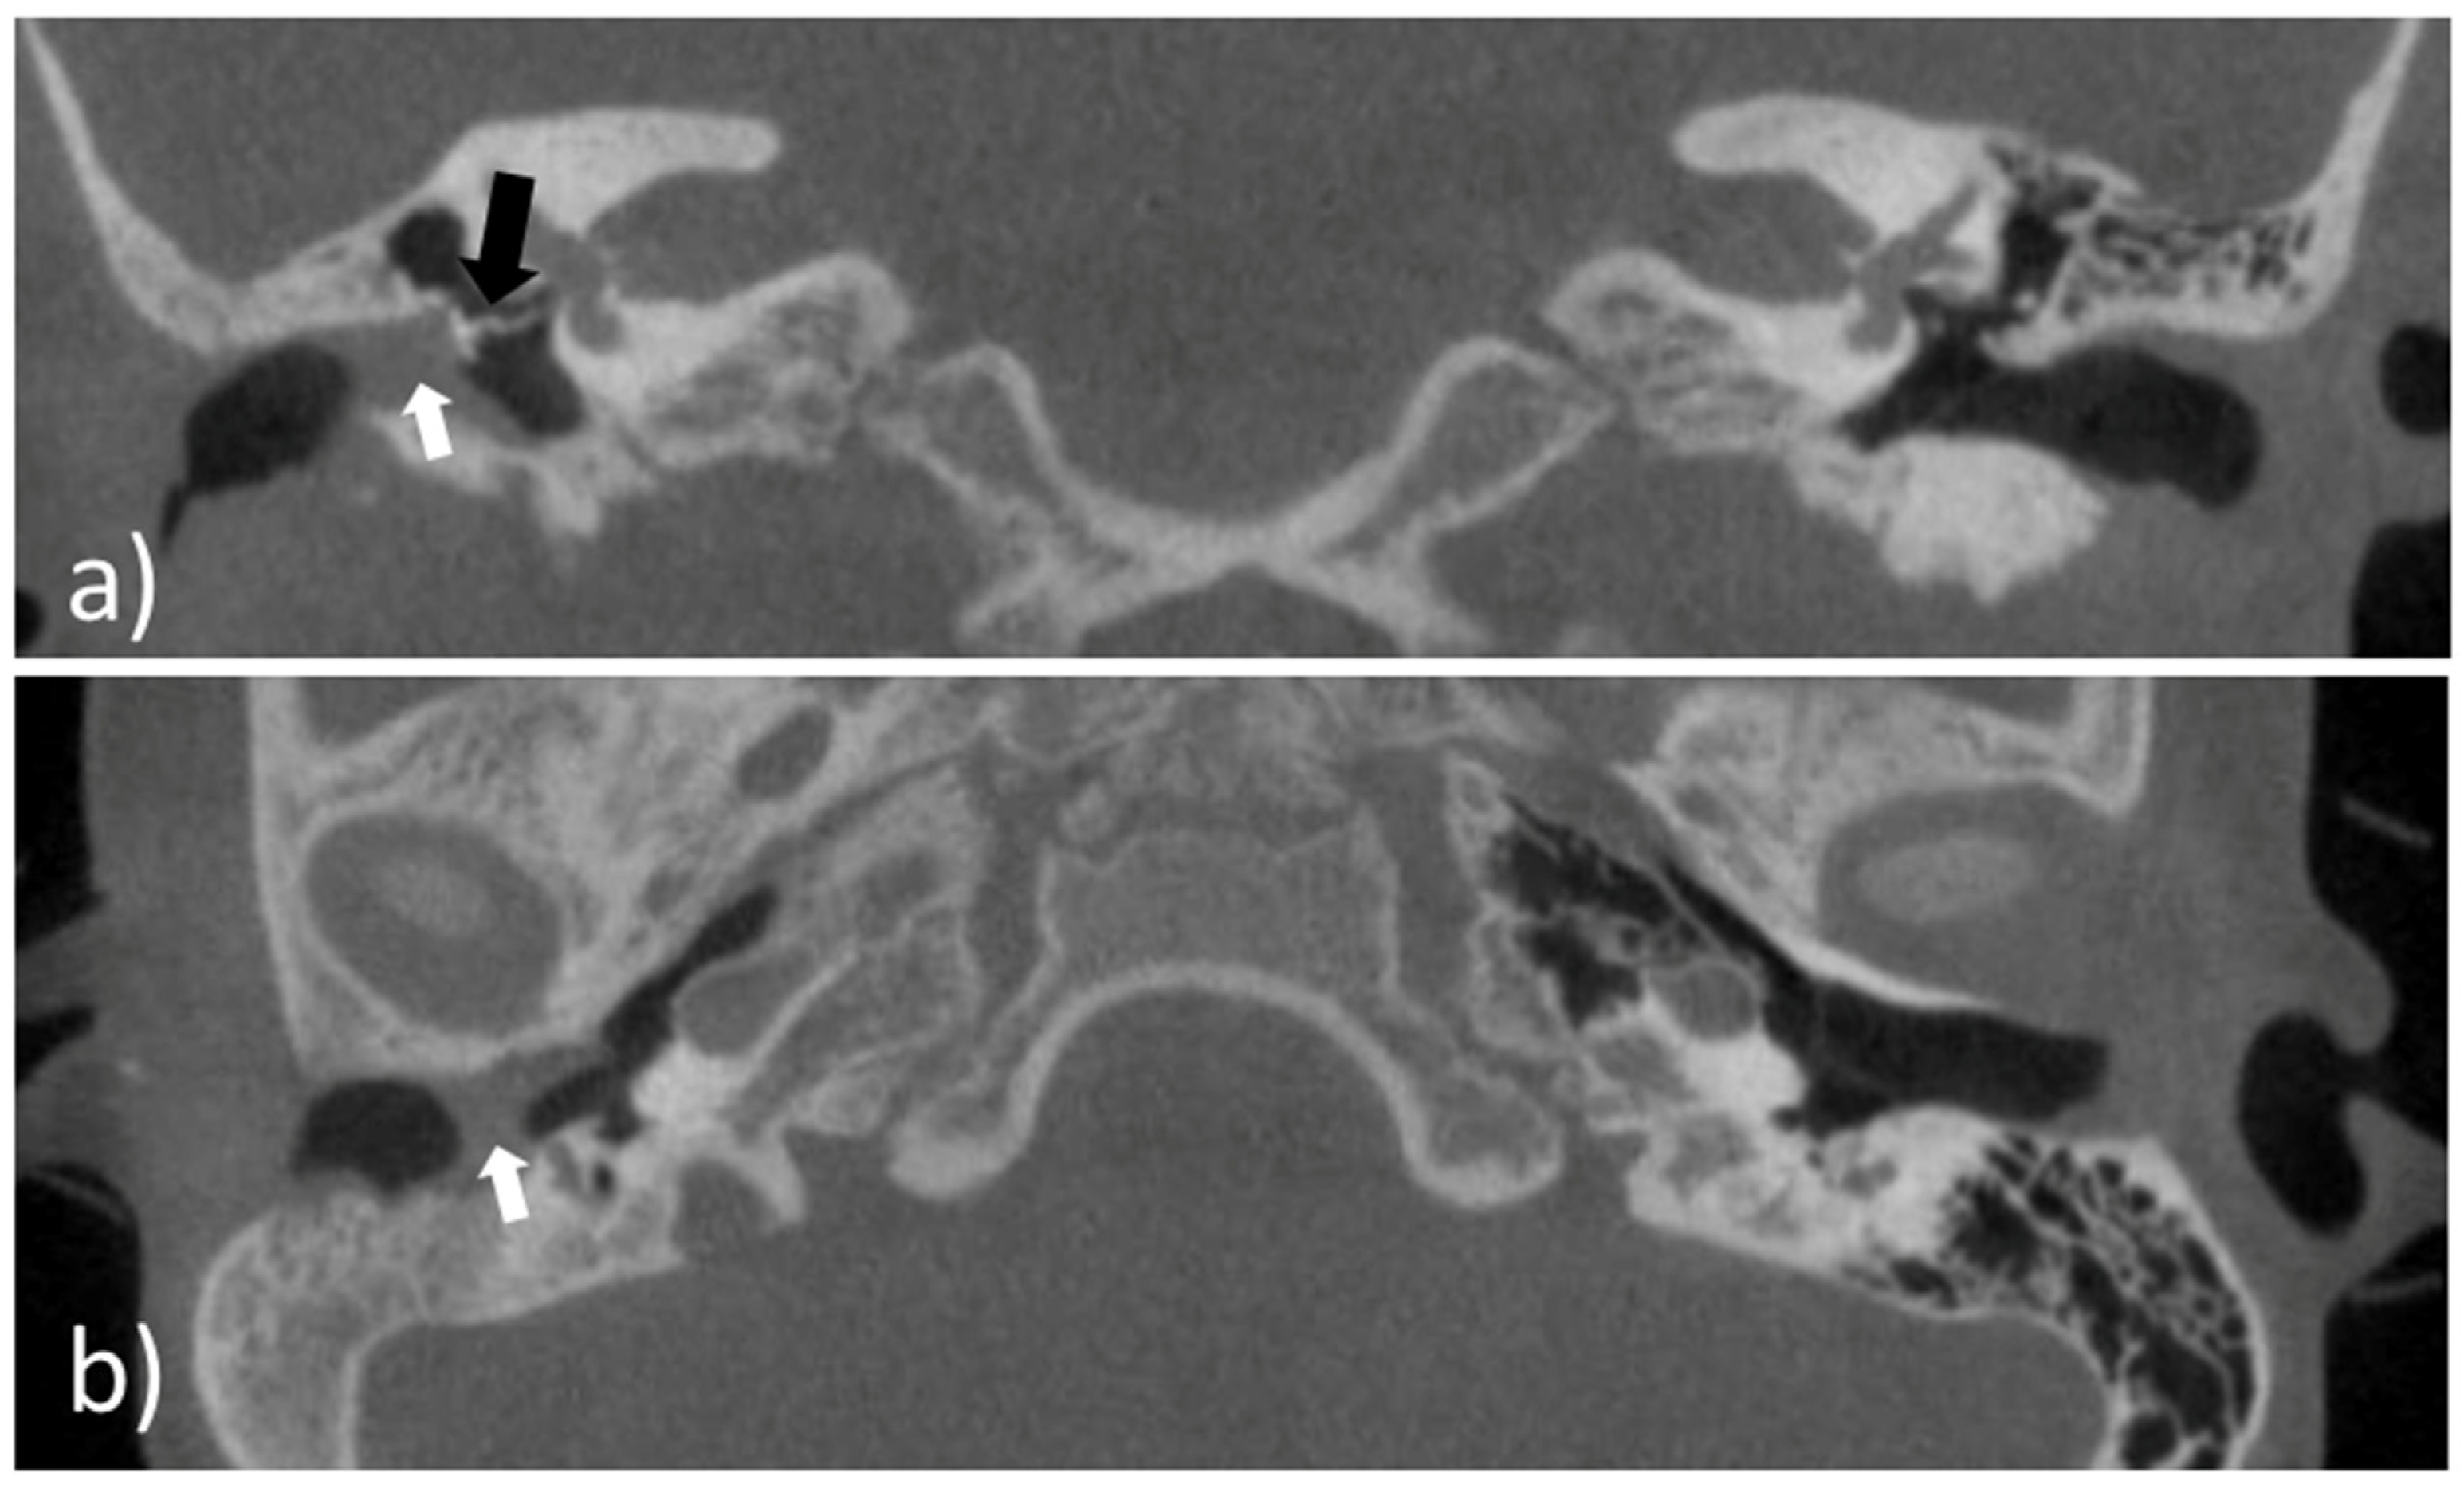

An eight-year-old girl with the diagnosis of unilateral congenital microtia and atresia of the EEC on the right side presented to our tertiary care hospital in January 2021. She had a patient history of multiple surgeries including reconstruction of the bony EEC and tympanoplasty type IIIa on the right in May 2018 and two revision canaloplasties with tympanic membrane (TM) reconstruction after restenosis of the EEC on the right side in January 2019 and September 2019. The clinical exam showed a partial restenosis of the surgically constructed EEC on the right side. A cone beam computed tomography imaging of the temporal bone (CBCT; xCAT, Xoran Technologies, Inc., Ann Arbor, MI, USA) (Figure 1) demonstrated a partial restenosis of the EEC on the right, but an aerated middle ear space, a middle ear partial ossicular replacement prosthesis (PORP), and an aberrant facial nerve course.

Prior to the preclinical testing, the patient presented to our outpatient clinic. CBCT imaging of the temporal bone was performed (Figure 1) to capture the anatomy of the region of interest (ROI). The acquired data were saved as image slices in the DICOM (digital imaging and communications in medicine) format and the ROI was segmented manually by a trained ENT surgeon using 3D SlicerTM version 4.11 (Surgical Planning Laboratory, Brigham and Women’s Hospital, Harvard Medical School, Boston, MA, USA) (http://www.slicer.org; accessed on 1 November 2021) to build a 3D reconstruction of the bony EEC. The segmentation resulted in the isolation of the ROI through a semi-automatic process based on region thresholding of the bony edges of the EEC (Figure 2a). After segmentation, the implant surface was processed by applying the surface smoothing effect with the dimensionless parameter of 0.5 in 3D SlicerTM. All reconstructions were transformed into a hollow object with a wall thickness of 1.5 mm and then the ends facing to the TM and the opening of the EEC were cut. Subsequently, a stereolithography (STL) file of the digital model was generated (Figure 2b).

Figure 1. Cone beam computed tomography imaging of the temporal bone of the patient. (a) Coronal view of the external ear canal with the white arrowhead pointing to the restenosis; an aerated middle ear space and a middle ear partial ossicular replacement prosthesis (black arrowhead); (b) axial view of the external ear canal with the partial restenosis (white arrowhead).